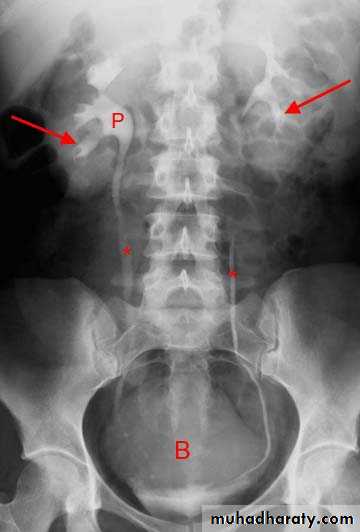

Interpretation of IVU films (what to look for?):

The kidneys:Check their position (left kidney is usually higher).

Identify the whole of both renal outlines, look for any indentations or bulges:

Renal parenchymal width should be uniform (2-2.5cm)

measure renal lengths: Normal length of adult kidney at IVU is 10-16cm. This is higher than in ultrasound due to image magnification.

2.Calyces:

-should be evenly distributed -symmetrical.-Cup shaped (normal shape) -Club shaped (when dilated)

3. Renal pelvis and ureter:

-The normal renal pelvis and pelvi-ureteric junction are funnel shaped.-Ureters are seen only in part of their length on any one film due to obliteration by peristalsis.

4. Bladder

The bladder is a centrally located structure.Smooth in outline.